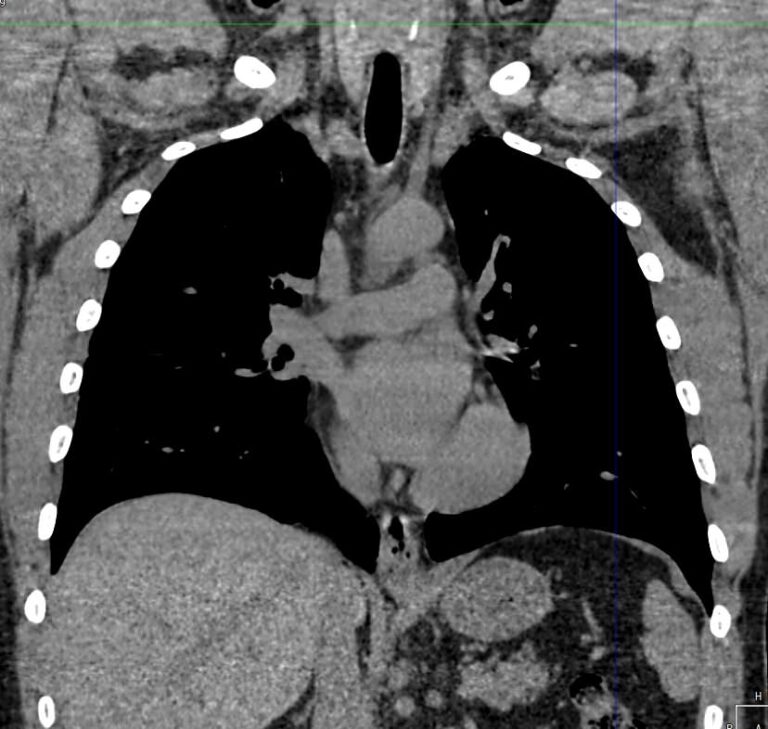

Одним из наиболее информативных методов исследования органов средостения является компьютерная томография. В основе метода лежит использование проникающего действия ионизирующего излучения для получения подробных снимков строения внутренних органов.

Инновационные технологии, которыми оснащены компьютерные томографы, послойно сканируют анатомическую область с шагом от 0,5 мм. В результате получаются снимки тонких срезов исследуемой зоны в мельчайших подробностях. С помощью цифровых приложений на основании полученных данных можно реконструировать трехмерные модели внутренних органов, что позволяет оценить структуру зоны исследования и близлежащих тканей.

- Что показывает КТ органов средостения?

Что показывает КТ органов средостения?

- наличие онкологии и метастазов;

- туберкулез и другие инфекции;

- патологии диафрагмы и бронхов;

- последствия травм;

- состояние лимфоузлов;

- индивидуальные анатомические особенности;

- патологии вилочковой железы;

- новообразования из нервной ткани;

- опухоли в жировой соединительной ткани;

- патологии мышечной ткани и сосудов;

- кисты;

- эмфизему средостения;

- абсцесс, эмпиему средостения;

- аневризму аорты

- воспалительные процессы;

- болезни сосудов и тромбоэмболию.